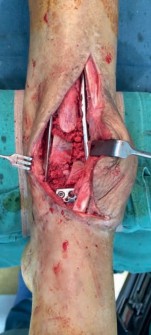

Avoided through a combination of prophylactic antibiotics, extreme care with soft tissues, and reducing duration of surgery (Fig 2.2-7).

Fig 2.2-7a–e Example from a different case of infection and flap necrosis complicating pilon fracture ORIF, managed with staged bony and soft-tissue reconstruction. An acute infection was diagnosed on postoperative day 3 (a). The patient

underwent multiple debridement surgeries with retention of implants (b); cement spacer implantation for dead space and infection management (c); free flap reconstruction for soft-tissue coverage; Masquelet-induced membrane technique and iliac crest bone grafting of the metaphyseal defect (d). A good

functional outcome with healed fracture and free flap at 15 months postoperatively (e).